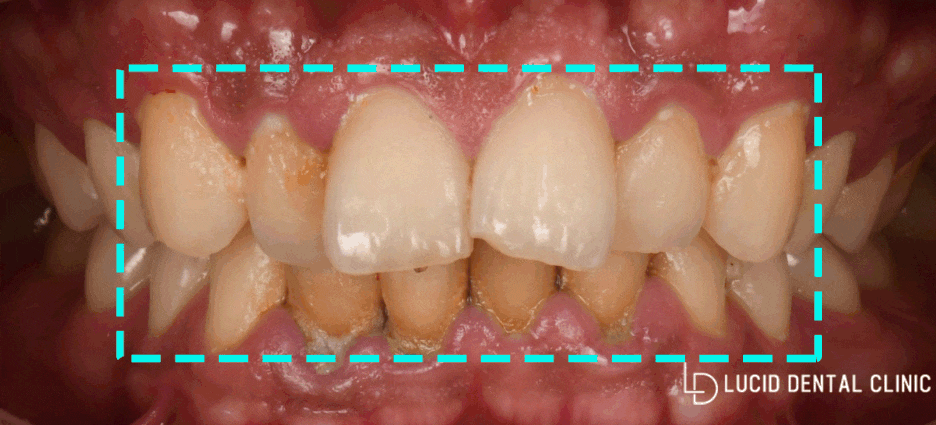

오늘 논현동 치과 에서

소개해 드리는 사례 속 환자께선

치주 질환 및 누렇게 변한 색이

고민이라며 찾아오셨습니다.

곧바로 정밀 구강 검진을 시행한 결과,

아래와 같은 모습을 볼 수 있었습니다.

-

치주 질환으로 잇몸 퇴축

불규칙한 치열

여러 가지 이유로 착색된 치아들

위와 같은 문제들로 인해

충치 질환은 물론, 이시림 증상이 나타나

정상 생활에 방해를 줄 수 있는데요

특히 고르지 못한 치열과 길이, 그리고 착색은

심미적으로 불편감을 줄 수 있습니다.